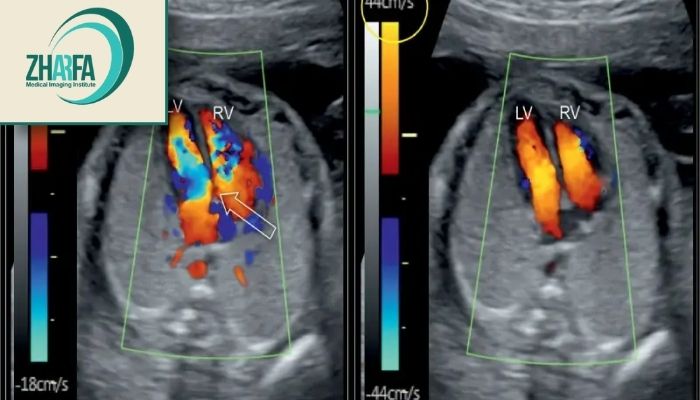

تشخیص ناهنجاریهای قلبی: این شیوه میتواند در تشخیص مشکلات مربوط به قلب مانند نارسایی دریچهها و اختلالات دیگر مفید باشد.